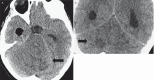

Lhermitte-Duclos disease is a rare pathologic condition consisting of a dysplastic gangliocytoma of the cerebellum. Its association with phacomatosis and an autosomal dominant neoplastic syndrome, Cowden's syndrome is also known. Modern neuroimaging contributes to a correct diagnosis and pre- and postoperative evaluation. Here we describe the morphologic and metabolic aspects of the disease as shown by conventional MRI, diffusion imaging and spectroscopy in a 31-year-old woman. In addition, the specific neuroradiologic characteristics are presented and discussed in the light of the main pathologic and clinical features, such as hypertrophy of the cerebellar folia associated with white matter atrophy.